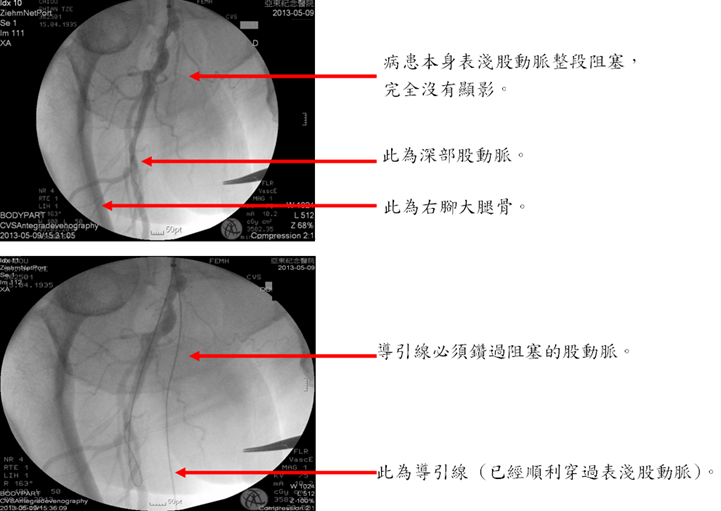

本院心臟血管外科在引進先進的手術室血管攝影設備之後,便極力整合血管內治療與外科手術兩方面。 一個病人,在同樣一次的麻醉程序中,在超音波導引之下,在血管內放入導管。先以血管攝影確認診斷與必須處理的部位,然後對於適合血管內治療的部位施以氣球擴張或支架置放術, 對於適合手術治療的部位,則施以繞道手術。如此一來,患者的下肢動脈阻塞疾病可以在最短的時間內一次解決,肢體保留的機會自然增加,省去了常令患者極度沮喪的截肢。